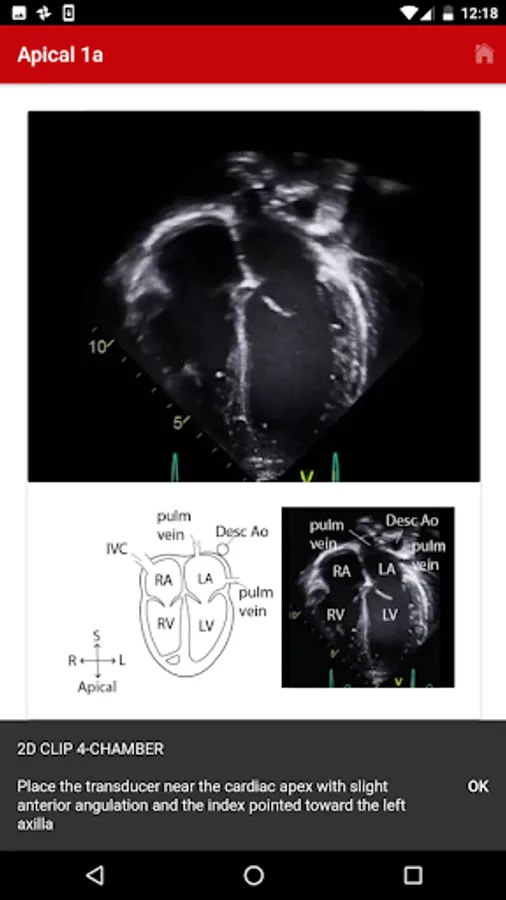

3. Apical

The exact images and the order in which the images and views are obtained varies by institution. Each protocol (subcostal, parasternal, apical or suprasternal) can be followed in order by clicking on the next tab at the bottom of the page or you can click on an individual numbered view within the protocol list to be taken directly to that view. The name of the view and instructions will pop-up automatically at the bottom of the page. The instructions and additional notes can also be found in the “NOTE” button at the bottom of the page.